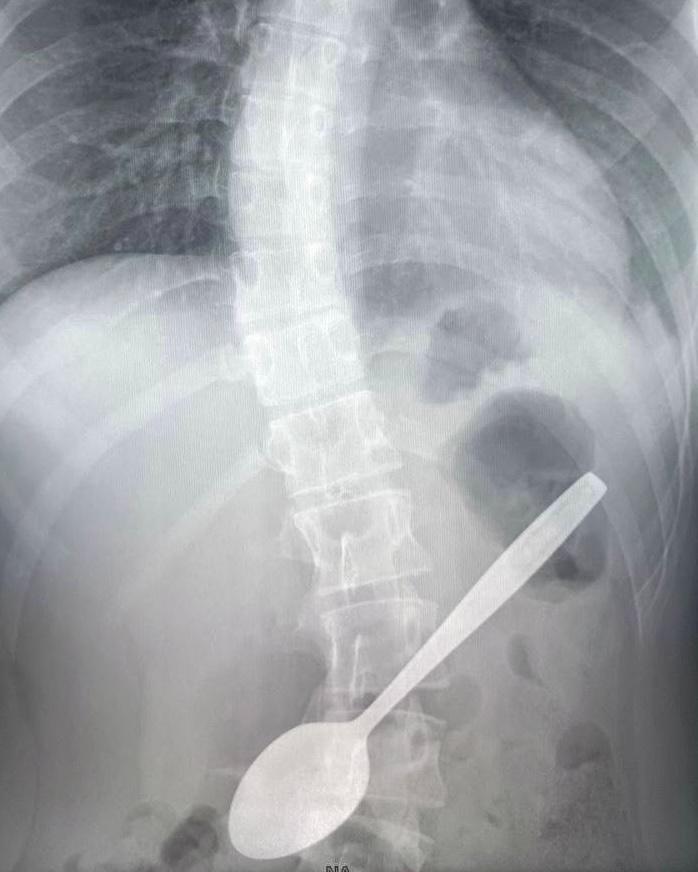

проглотил стекло

Что будет если случайно проглотил стекло 107 фотографий